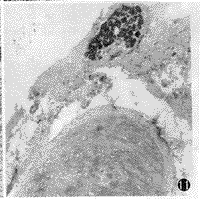

图10 可见较发达的似为泪腺的粘液性腺,且有完整的导管系统 HE×200

图11 示透明软骨 HE×200